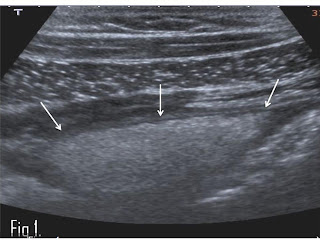

The ultrasound features of acute omental infarction include a well-circumscribed triangular or oval heterogeneous non compressible fatty mass with an echogenic alteration of the fat between the anterior abdominal wall and the transverse or ascending colon (Figure 1). The echogenic area of infarction may contain focal areas of hypo-echogenicity as well. Often this pseudo-tumour is fixed to the abdominal wall, readily identified during real-time ultrasound examination. With acute appendicitis a round non compressible tubular ending structure with a diameter of more than 6mm is usually identified on ultrasound, easily allowing differentiation from the echogenic mass of acute omental infarction seen on an ultrasound examination. With diverticulitis of the ascending colon an echogenic "out-pouching” of the colon with alteration of the surrounding fat is visualized on ultrasound.

Figure 1:A transverse view on ultrasound of the right lower quadrant in a 22 year old male patient with severe pain in this area. A 4 cm echogenic lesion is fixed to the abdominal wall (arrows). No movement of the lesion in regard to the hypo-echogenic abdominal wall muscles was seen during real time scanning.